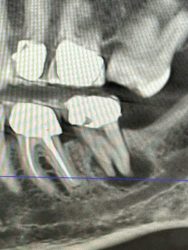

Case I got yesterday. Patient really wants an implant at #18 site. Fun case! ~60yo female, non-smoker, no DM, no osteoporosis or any other bone-related diseases.

How does one clean that PARL adequately, avoid disturbing the IA, and graft reliably. That is a fun case!